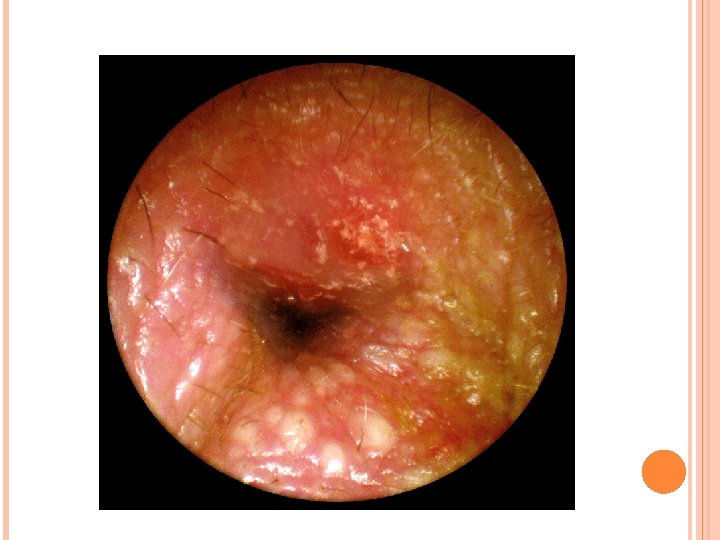

Otitis externa difusa (Pseudomona) Es una inflamación del CAE por pseudomona aeurginosa. Son más frecuentes en verano debido a los baños, ya que el agua que entra en los conductos y la humedad repetida favorece este tipo de infección, también en personas con más sudoración o en limpieza excesiva de los oídos que ocasiona escasez de cerumen que actúa como protector manteniendo el p. H adecuado de la piel. Los síntomas son otalgia y otorrea seropurulenta. A la otoscopia hay inflamación de las paredes del CAE que impide a veces introducir el otoscopio, y secreción seropurulenta. Tratamiento se realiza con gotas de ciprofloxacina con corticoide y añadir antibióticos y antiinflamatorios por vía sistémica. No mojar los oídos.